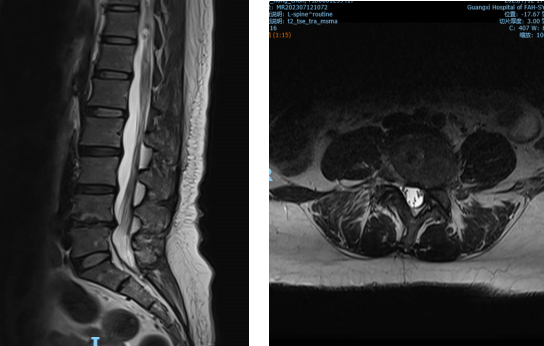

▲②术前MRI片

“医生,我这半年来腰痛的厉害,右腿现在又痛又麻,走路都困难,有什么办法处理吗?”在骨科诊室,患者谭阿姨(化名)苦恼地说道。皇冠足球网 骨科脊柱外科专业专家欧裕福副主任医师详细询问谭阿姨病史,并为她安排了细致的检查,最终诊断为腰椎管狭窄症+腰椎滑脱症。

结合谭阿姨下腰部明显压痛、右下肢疼痛及活动障碍等症状,骨科脊柱外科团队经过多次术前讨论,并联合麻醉手术中心团队,为谭阿姨制定了个性化的诊疗方案,决定运用经皮内镜下腰椎减压融合技术为患者进行治疗。